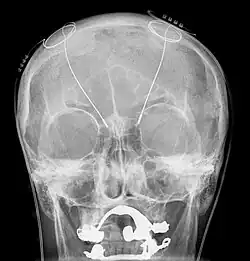

The leads are two coiled wires insulated in polyurethane with four platinum-iridium electrodes that allow delivery of electric charge from the battery pack implanted in the chest wall. The battery is usually situated subcutaneously below the clavicle and rarely in the abdomen. The leads, in turn, are connected to the battery by an insulated extension wire which travels from the chest wall superiorly along the back of the neck below the skin, behind the ear, and finally enters the skull through a surgically made burr hole to terminate in the deep nuclei of the brain.[20] Microelectrodes (usually 1–5) are delivered through the burr holes. A combination of microelectrode recordings, microstimulation, macrostimulation, and neurophysiological mapping at the level of single neurons or local neuronal populations through local field potential analyses are used to increase specificity of placement for the most precise neurophysiologic effect possible.[2]

DBS leads are placed in the brain according to the specific symptoms to be addresses and implantation may take place under local or general anesthesia. A hole about 14 mm in diameter is drilled in the skull and the probe electrode is inserted stereotactically, using either frame-based or frameless stereotaxis.[22] During the awake procedure with local anesthesia, feedback from the individual is used to determine the optimal placement of the permanent electrode. During the asleep procedure, intraoperative MRI is used to image the brain during device placement.[23] The installation of the IPG and extension leads occurs under general anesthesia.[24]

Because the brain can shift slightly during surgery, the electrodes can become displaced or dislodged, though electrode misplacement can be suspected by lack of clinical effect when the leads are turned on and a sudden dramatic increase in electrode impedance. The displacement can be physically located using CT scan, which would then guide a repeat intervention for repositioning. After surgery, swelling of the brain tissue, mild disorientation, and sleepiness are normal. After 2–4 weeks, the sutures are removed and the neurostimulator is activated.[156]